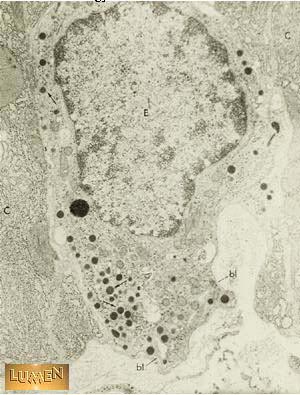

If this is an EM of an endocrine cell in the wall of a gastric gland, what is this cell secreting into?

Capillaries in the lamina propia